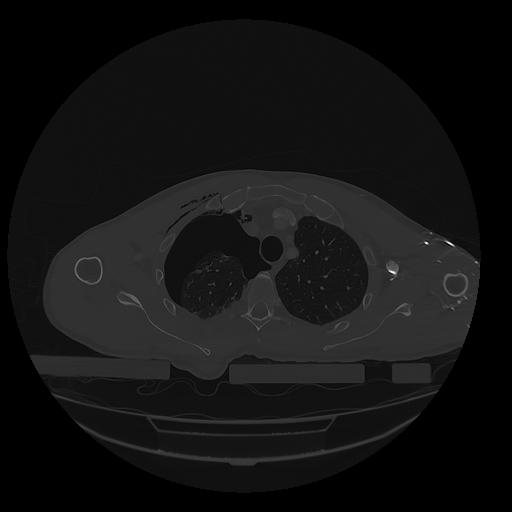

31 PULMON,CE,Vol,1.0,PULMON,,